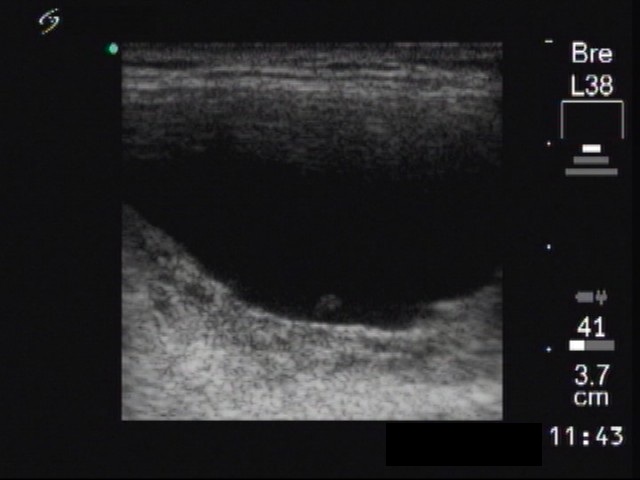

Ethanol sclerotherapy: thyroid cysts - Case 6

First session of therapy (ultrasonographic picture 3)

Right lobe, another longitudinal scan.